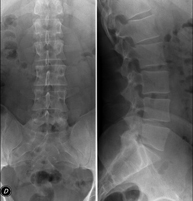

- Lumbar spine X-ray

This technique uses X-ray rendered imaging to examine the lumbar spine. Indicated for: sciatica, trauma, lower back pain.